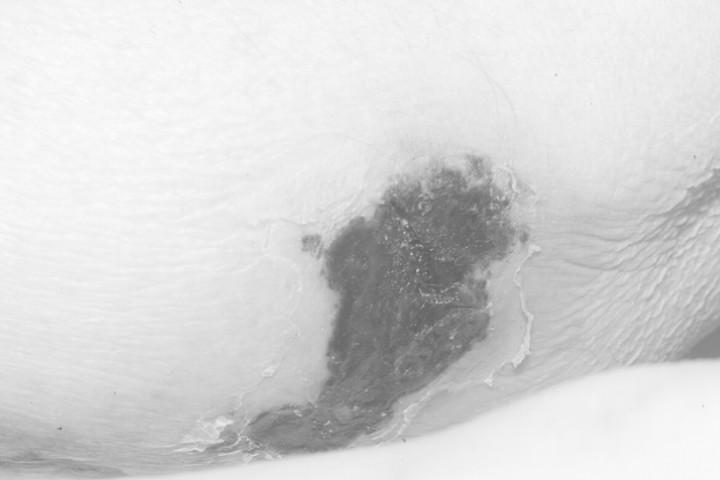

A painful skin rash in a patient with Stage V chronic kidney disease.